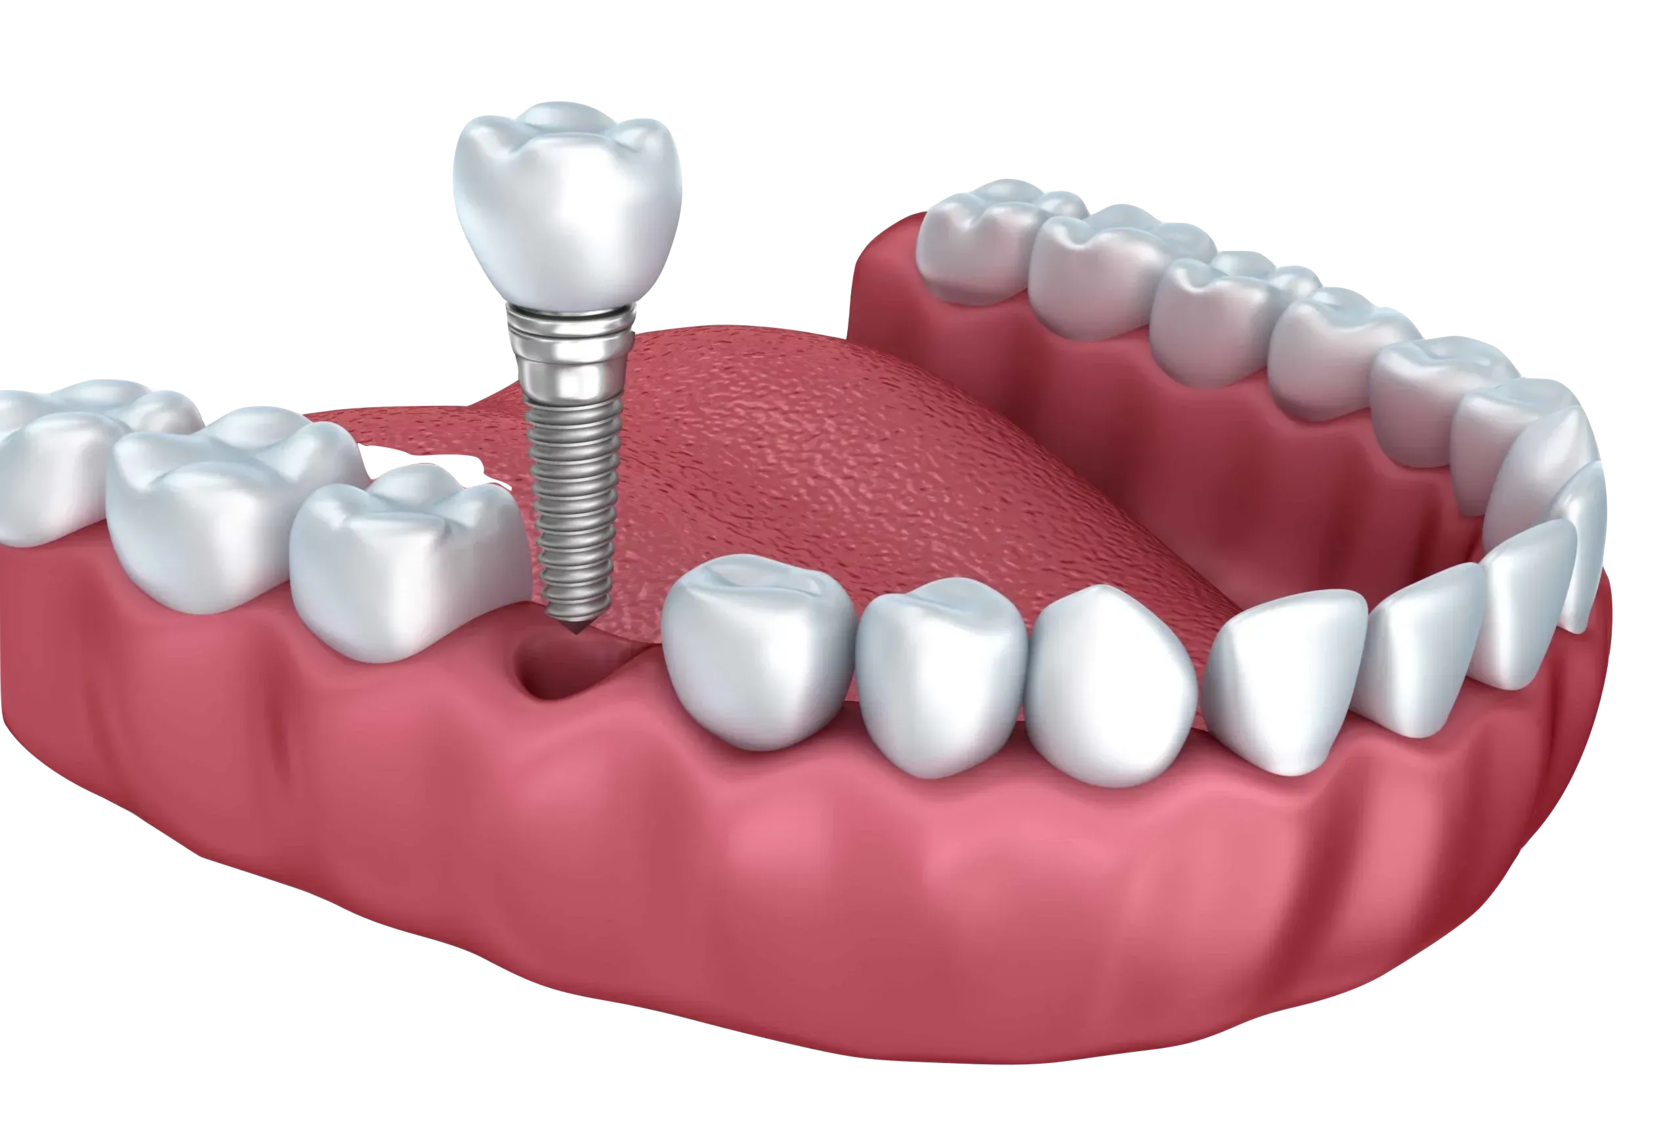

Total oral rehabilitation with implantation and crowns

Total oral rehabilitation with implantation and crowns